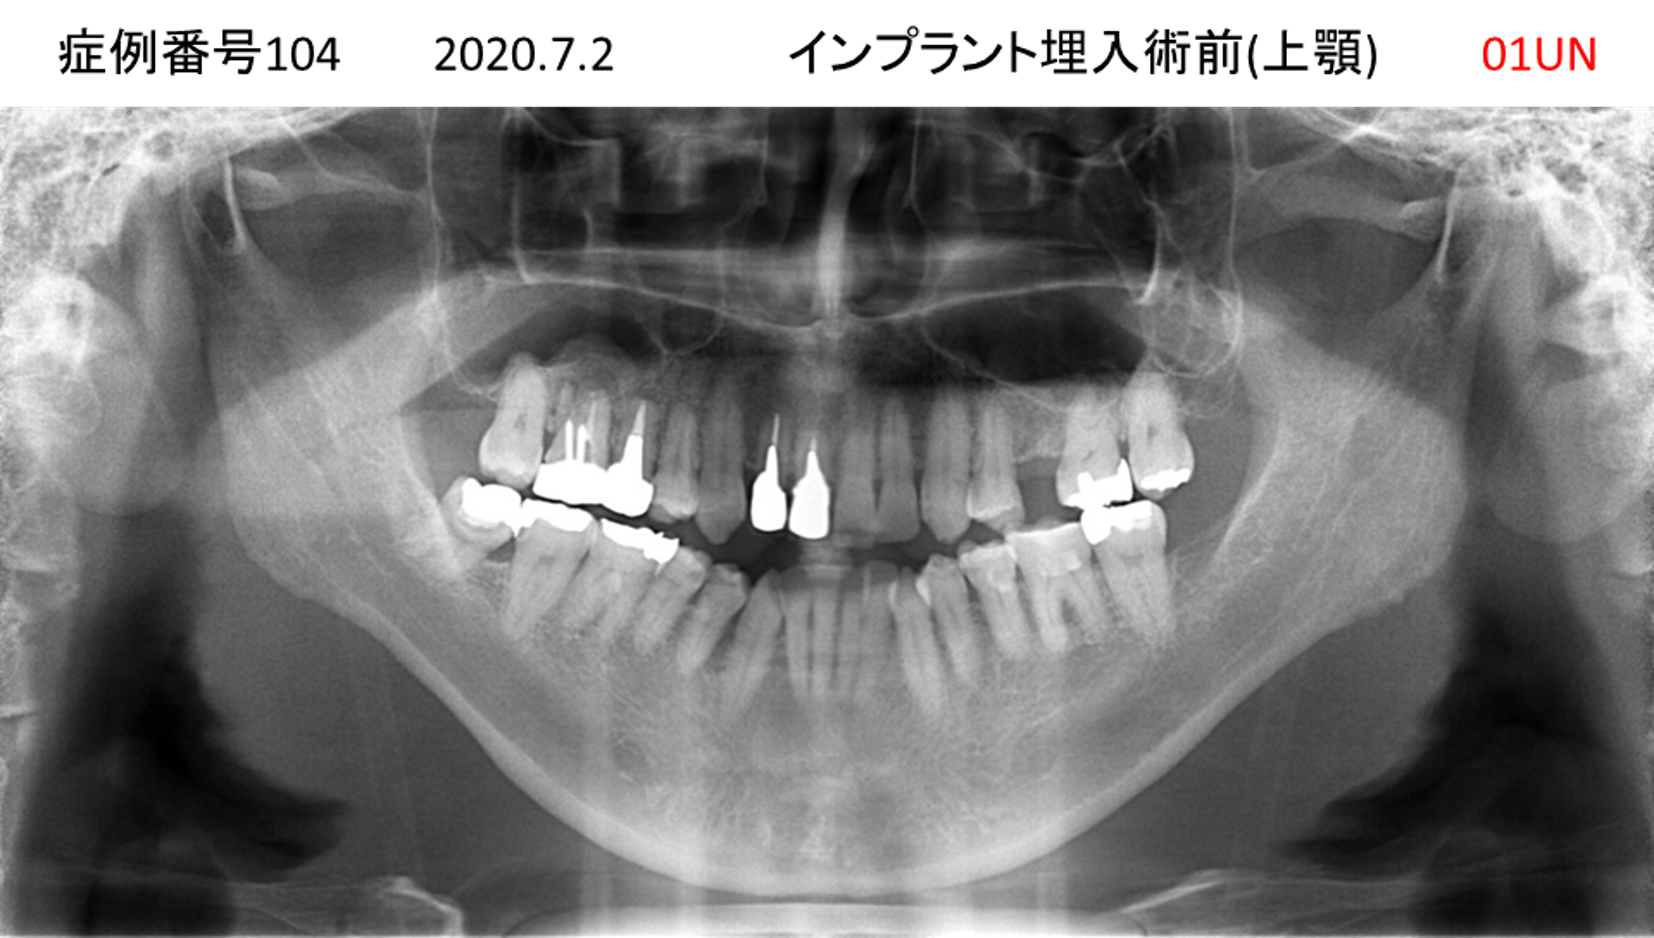

上の前歯が揺れてきてかめない患者様のインプラント症例

| 治療名称 |

インプラント |

| 治療費用 |

440万円+税 |

| 治療期間 |

6か月 |

| 患者さんの症状(主訴) |

上の前歯が揺れてきた。かめない |

| 治療内容 |

サイナスリフト、GBR、インプラント、即時荷重 |

| 治療結果 |

上の前歯の揺れが収まった。奥歯でしっかり噛める。 |

| 治療の注意点(リスク/副作用) |

インプラントが壊れたら再治療が必要 |